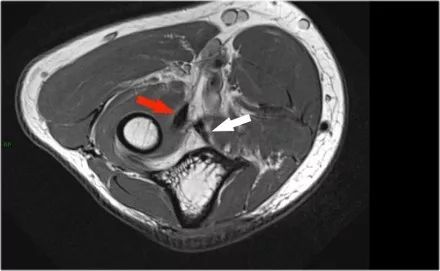

下面是另一种情况。在矢状图像上,我们不确定可能的撕裂。也许只有一些肌腱炎或肌腱炎。轴向图像显示部分撕裂(红色箭头)。

始终确保你的轴向扫描一直到结节,因为你太早停止,就像在这种情况下,你只会看到增厚的肌腱和一些液体,但你不确定可能的撕裂。